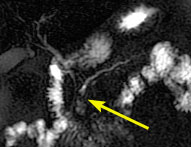

Immediately after injection of gadolinium contrast agent, the mass shows reduced enhancement. Arrow incidates the uninvolved superior mesenteric artery.

Approximately 30 seconds after injection of contrast agent, the superior mesenteric vein is shown (arrow).